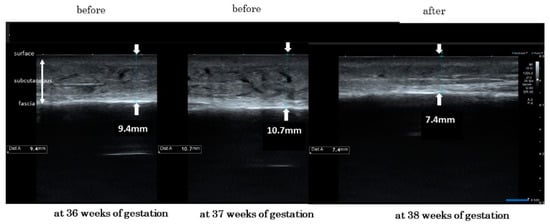

3.2. Level Changes of the Lower Leg Skin Thickness from before to after the Wearing of Elastic Compression Stockings